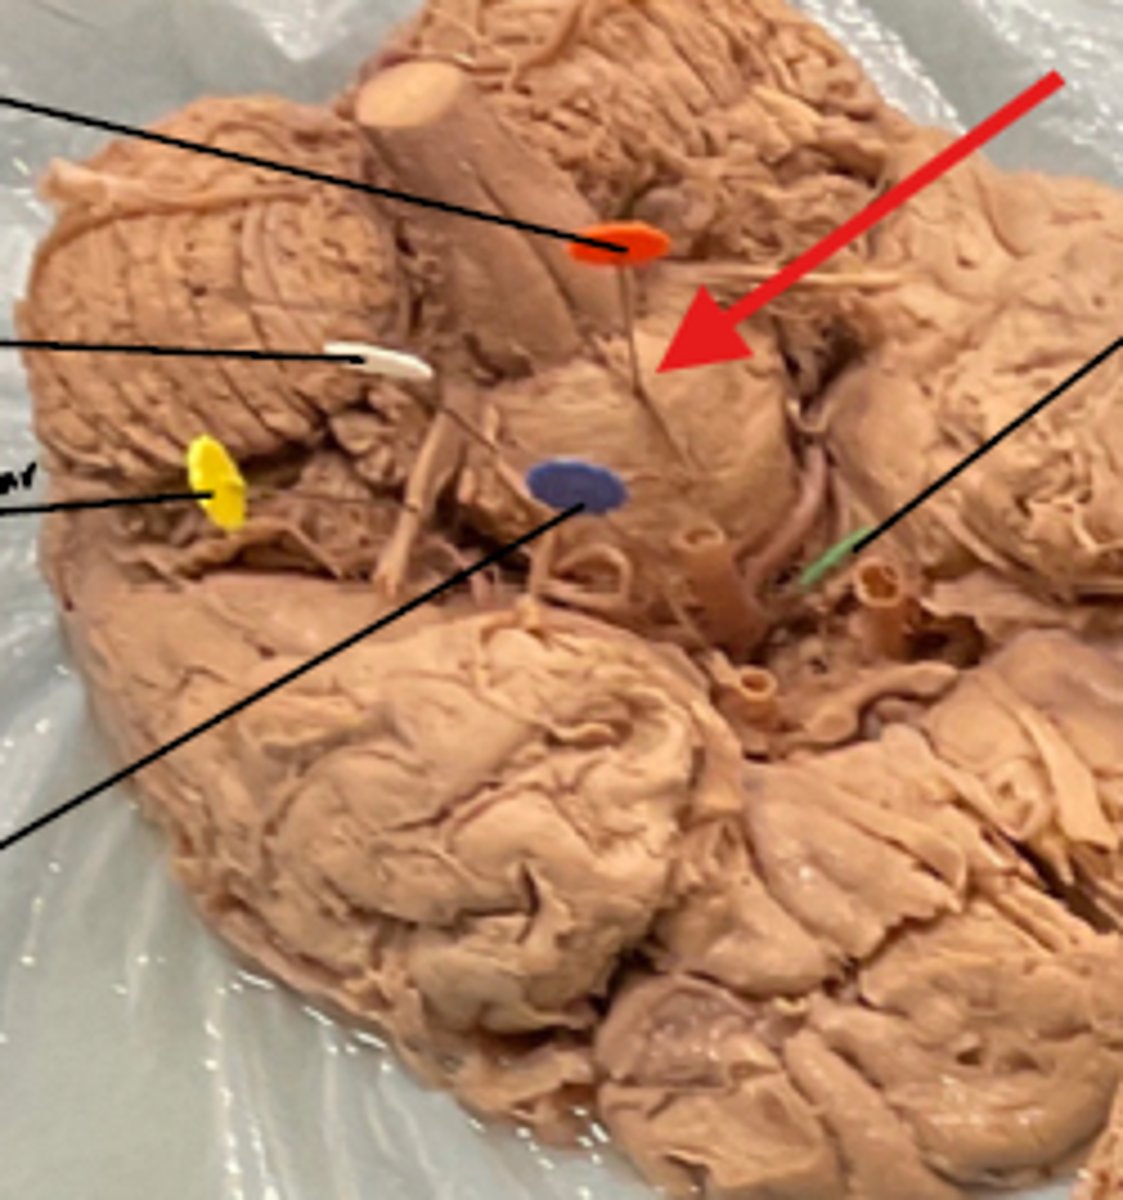

What is the blue arrow pointing at?

What space is the yellow arrow pointing to?

What part is the yellow arrow pointing to?

what space is the yellow arrows pointing to?

what is the yellow arrow pointing at?

what is the blue circle surrounding?

Name the structure the yellow dot is on.

what structure is the blue pin in?

What is number 50 or the blue dot?

blue arrow is pointing to which structure?

The area the blue arrow is pointing to?

structure blue arrows are pointing to?

What area is the blue arrow pointing to?

Where is the yellow arrow pointing to?